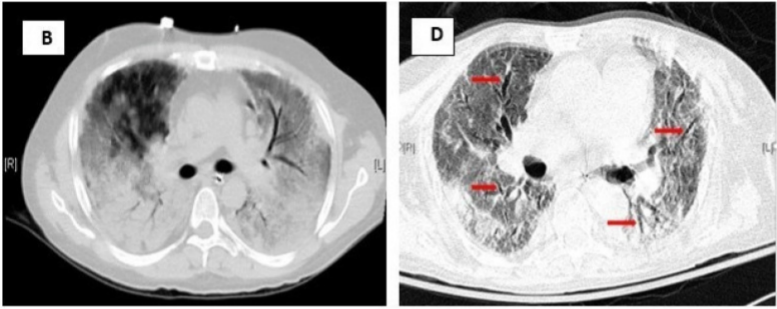

肺通气的超声征象分为四组:①正常模式(N),表现为肺滑动征伴A线或孤立的B线(<3),记0分;②肺通气中度丧失,出现多条B线(>3),记1分;③严重的肺通气损失,显示为融合B线,记2分;④肺组织实变征象记3分。在分析过程中,每一个特定的区域最差的超声波征象为计分标准,并将所有点的得分相加。结果显示,肺部超声评分(LUS)与多个ARDS预后指标[血管外肺水指数(EVLWI),肺损伤评分(lung injury score,LIS),呼吸系统顺应性(Crs),氧合指数]密切相关,能够准确评估ARDS治疗的疗效,如PEEP的设定、肺复张的疗效,并能够预测ARDS患者死亡风险。与其他检查相比,肺部超声是一种无创、经济、可重复、简单的床旁检查方法,但肺气肿、肥胖、导管敷料等都影响超声的评定,测量参数有一定的主观性。弥漫性肺泡损伤(DAD)是ARDS的病理标志。一项研究分析了是否可以使用高分辨率CT(HRCT)评分来预测与DAD相关的60 d死亡率,研究共纳入34例在ARDS诊断后7 d内接受HRCT的DAD患者,并被分为60 d存活组和未存活组,每组17例患者。采用Ichikado等提出的HRCT评估急性间质性肺炎评分系统评估ARDS,HRCT表现根据分级系统按1~6分进行评分,1分为正常衰减,2分为磨玻璃影,3分为实变,4分为磨玻璃影伴牵引性支气管扩张或细支气管扩张,5分为实变伴牵引性支气管扩张或细支气管扩张,6分为蜂窝状。单因素和多因素二元回归分析以及ROC曲线显示,牵引性支气管扩张或细支气管扩张的总面积百分比是60 d死亡率的独立预测因子,具有良好的预测性能。存活患者的HRCT表现为广泛的磨玻璃影和实变,支气管壁光滑(图4B)。未存活患者的HRCT表现为双侧磨玻璃影、网状和明显的牵引性支气管扩张(图4D红色箭头)。图源:J Clin Med, 2022, 11(9):2458.肺部炎症是ARDS的关键特征之一。氟代脱氧葡萄糖(FDG)是一种具有生化活性的葡萄糖抗代谢产物,FDG被组织细胞吸收后可在PET-CT扫描显像。中性粒细胞活化在代谢上的特征是每个细胞的葡萄糖利用率增加,从而增加FDG摄取。在急性肺损伤(ALI)期间,FDG PET可用于监测肺中性粒细胞活化情况。同时,在ALI状态下,巨噬细胞对FDG信号的变化较小,淋巴细胞在体外激活后FDG摄取增加。内皮细胞活化后具有高度代谢活性,摄取FDG增强,肺泡上皮细胞受损后也可以促进FDG的摄取。因此,FDG PET可能是一种有价值的非侵入性方法,可用于全面了解ALI/ARDS的发病机制,早期预测ARDS的发生和评估预后。研究发现,单侧吸入烟雾导致急性损伤的单侧绵羊肺中区域FDG摄取显著增加(图5,图6)。在该模型中,区域FDG标记葡萄糖摄取可以预测区域气体交换损伤,表明存在功能-炎症关系。研究结果还表明,损伤前的通气-灌注异质性程度与损伤后FDG摄取的程度之间存在直接关联。